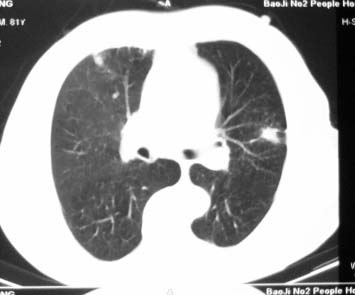

81 男 以头昏入院

两肺多发异常密度,其中双上肺病变主要为纤维增殖性改变;右中肺内侧段病变密度相对均匀,无恶性特征,周围可见卫星灶和浸润表现,邻近胸膜稍增厚,所见纵隔层面无肿大淋巴结和胸腔积液。提示结核性改变。如果可能建议强化。

两上肺纤硬病灶,左上肺炎症机化?

右肺中叶团片影,似多病灶融合而成,密度不均匀,边界清楚,周围见明显的索条及小结节,左肺亦见斑片影,纵隔窗未见肿大淋巴结.多考虑:肺内慢性炎性病变伴纤维化.

两肺多发异常密度,其中双上肺病变主要为纤维增殖性改变;右中肺内侧段病变密度相对均匀,无恶性特征,周围可见卫星灶和浸润表现,邻近胸膜稍增厚,所见纵隔层面无肿大淋巴结和胸腔积液。提示结核性改变.

符合多叶多段多形态的特点.

右肺中叶软组织块(挑剔一下纵隔窗窗宽不理想),其周围可见多个类圆形结节,右肺上叶尖段见斑片、索条状致影,左肺小结节。

1.右肺周围型肺癌伴肺内转移;

2.右肺上叶陈旧性结核;

3.左肺炎性结节;

右肺中叶软组织块,其周围可见多个类圆形结节,右肺上叶尖段见斑片、索条状致影,左肺小结节,见分叶、毛刺及胸膜凹陷征。1.左肺周围型肺癌伴右肺内转移; 2.右肺上叶陈旧性结核。

老年人,适用多元论,考虑 :1、左肺周围型肺癌伴右肺内转移; 2、右肺上叶陈旧性结核。